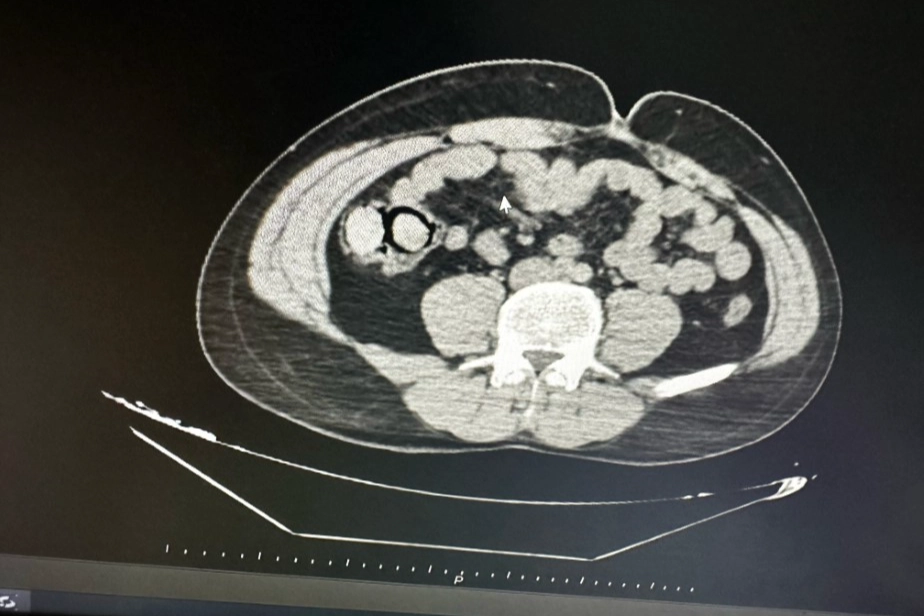

Bingöl Emniyet Müdürlüğü Narkotik Suçlarla Mücadele Şube Müdürlüğüne bağlı narko-timleri akıllara durgunluk veren bir uyuşturucu kaçakçılığını çözdü. Ekiplerin çalışmaları neticesinde otobüs ile Bingöl’e gelen şüpheli yabancı uyruklu 2 şahsın iç beden muayenesinde 10 parça halinde 113 gram metamfetamin maddesi tespit edildi. Emniyetteki işlemlerinin ardından mahkemeye çıkarılan 2 şahıs, uyuşturucu madde ticareti yapmak suçundan tutuklanarak Elazığ Kapalı ceza infaz kurumuna teslim edildi.